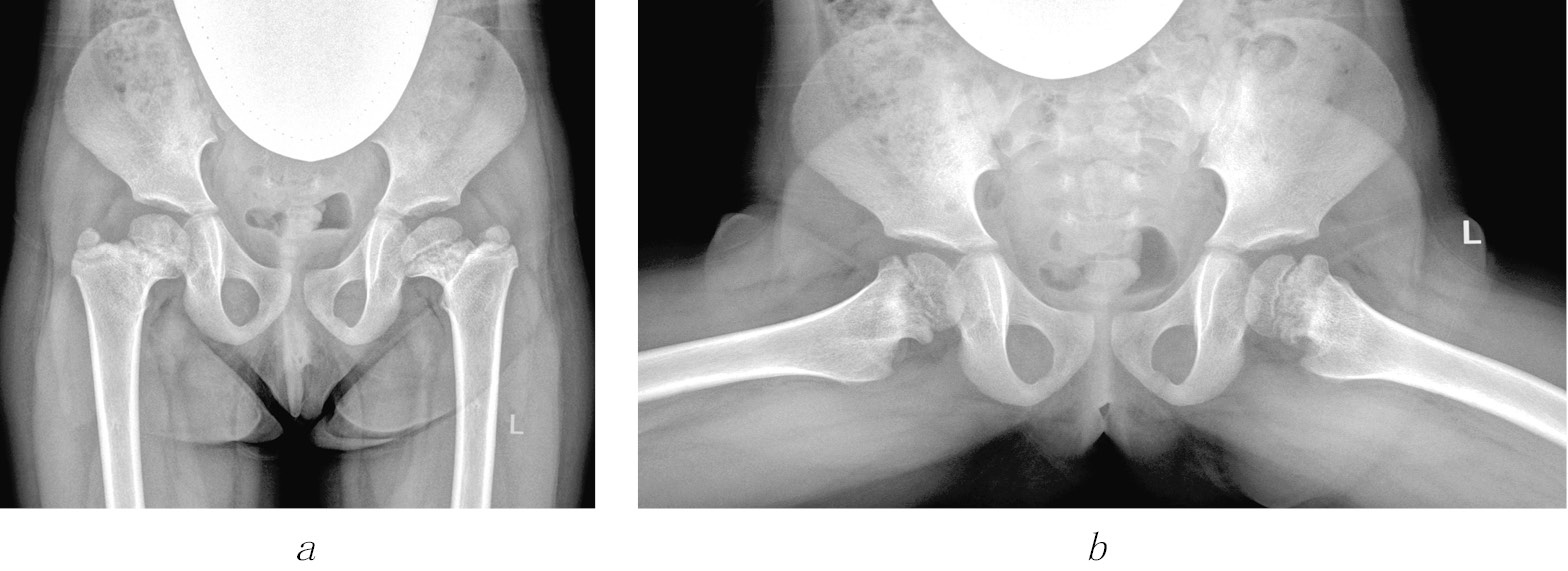

Рис. 3. Рентгенограммы пациентки Ш. Формирование многоплоскостной деформации проксимального отдела бедренной кости с высоким положением большого вертела после перенесенного аваскулярного некроза головки бедренной кости (справа — IV типа, слева — II типа по Kalamchi и MacEwen). В анамнезе — консервативное лечение по поводу врожденного вывиха бедра с двух сторон: а — в возрасте 1 года 2 месяцев; б — в возрасте 3 лет 9 месяцев; в — в возрасте 11 лет

2) последствия гематогенного остеомиелита (септического артрита) — 101 (28,9 %) ребенок. В эту группу также вошли пациенты, перенесшие внутриутробные инфекции и хирургические вмешательства на первом году жизни по поводу врожденных пороков сердца, атрезии пищевода, кишечной непроходимости, трахеопищеводных свищей, осложнившиеся инфекционным поражением тазобедренных суставов (рис. 4);

Рис. 4. Рентгенограммы пациентки Ж., 7 лет. Последствия гематогенного остеомиелита — многоплоскостная деформация проксимального отдела бедренной кости с высоким положением большого вертела слева: а — прямая проекция; б — проекция по Лауэнштейну